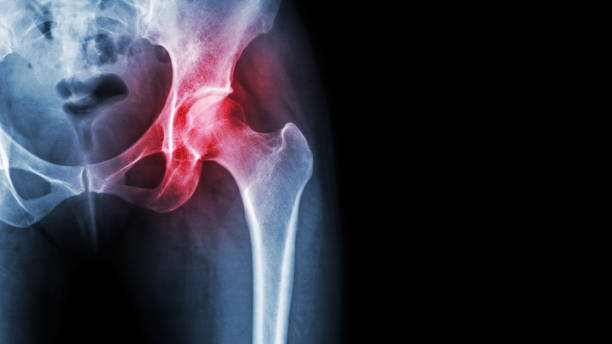

고관절 수술 후 회복에 필요한 시간을 알려드려요. 고관절 수술은 고관절의 변화로 인한 통증 및 기능 장애를 개선하기 위해 수술적인 처리를 하고, 수술 후 환자들은 회복 기간을 거치게 됩니다.

고관절 수술후 회복기간- 수술 후 1주일: 치료와 통증 관리

수술 후 1주일은 가장 중요한 시기입니다. 이 때에는 처음 수술에 대한 통증이 가장 심하며, 치료와 통증 관리에 집중해야 합니다. 수술 부위를 올바르게 관리하고, 의사의 지시에 따라 정확히 약물을 복용하는 것이 중요합니다. 또한, 특별한 동작을 하지 않도록 주의해야 합니다. 1주일 동안은 휠체어를 사용하거나 보조기를 사용하는 것이 좋습니다.